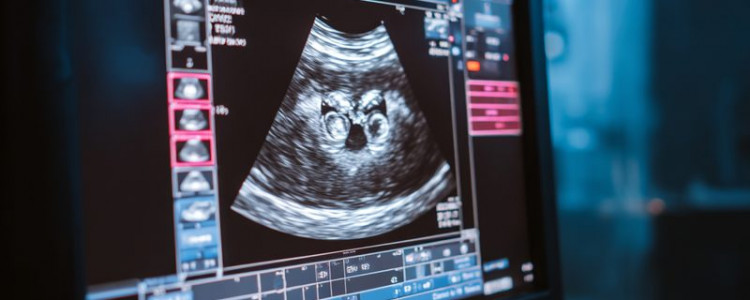

Комплексное УЗИ брюшной полости – это безопасный, безболезненный и высокоинформативный метод диагностики? Он позволяет оценить состояние органов между диафрагмой и тазовым кольцом, изучить их размеры, строение, эхоструктуру и толщину стенок? Процедура выявляет изменения, образования и позволяет увидеть работу органов в реальном времени, обеспечивая важный контроль за здоровьем?

Ультразвуковое исследование органов брюшной полости — ключевой и высокоэффективный метод диагностики в современной медицине? Его востребованность обусловлена неоспоримыми преимуществами и многогранными целями?

Среди главных достоинств процедуры — её абсолютная безопасность и безболезненность? УЗИ не использует ионизирующее излучение, что делает его безвредным для всех, включая беременных и детей, позволяя проводить исследование многократно без рисков? Это критически важно для динамического наблюдения?

Неоспоримое преимущество – высокая информативность? Ультразвук детально оценивает состояние внутренних органов: печени, желчного пузыря, поджелудочной железы, селезенки, почек, надпочечников, крупных сосудов, забрюшинного пространства? Врач определяет размеры, форму, структуру, толщину стенок, однородность эхоструктуры и наблюдает их работу в режиме реального времени? Это дает возможность своевременно выявить широкий спектр изменений: воспаления, кисты, конкременты и, главное, доброкачественные и злокачественные образования на ранних стадиях, когда терапия наиболее эффективна?